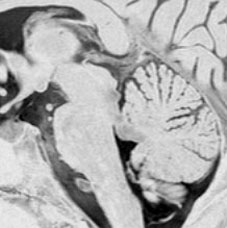

17歳で滑車神経麻痺で発症した例

中脳左下丘から上髄帆が腫大しています。滑車神経の出口にあたる部分が侵されていて症状と一致する所見です。右側のガドリニウム増強T1でも増強される部分はありません。確かにtectal gliomaの性質を有していて,3年間ほとんど動きませんでした。piaを押して突出するような腫瘤形成があり,diffuse astrocytomaともまた違う画像所見と言えます。滲み込む infiltrateというより,塊 solid massを作るという形質があるのがtectal gliomaでしょう。